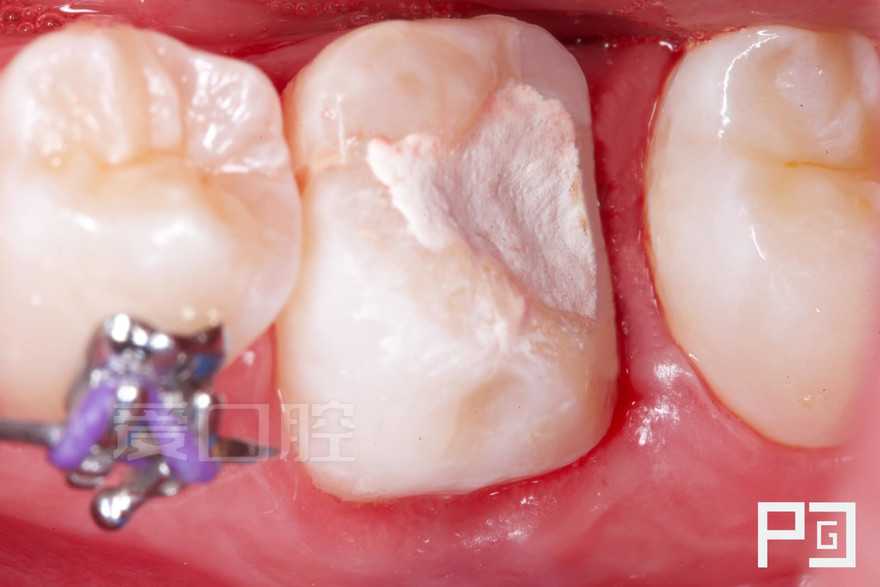

看个根充 —— 下6

by Paco CG